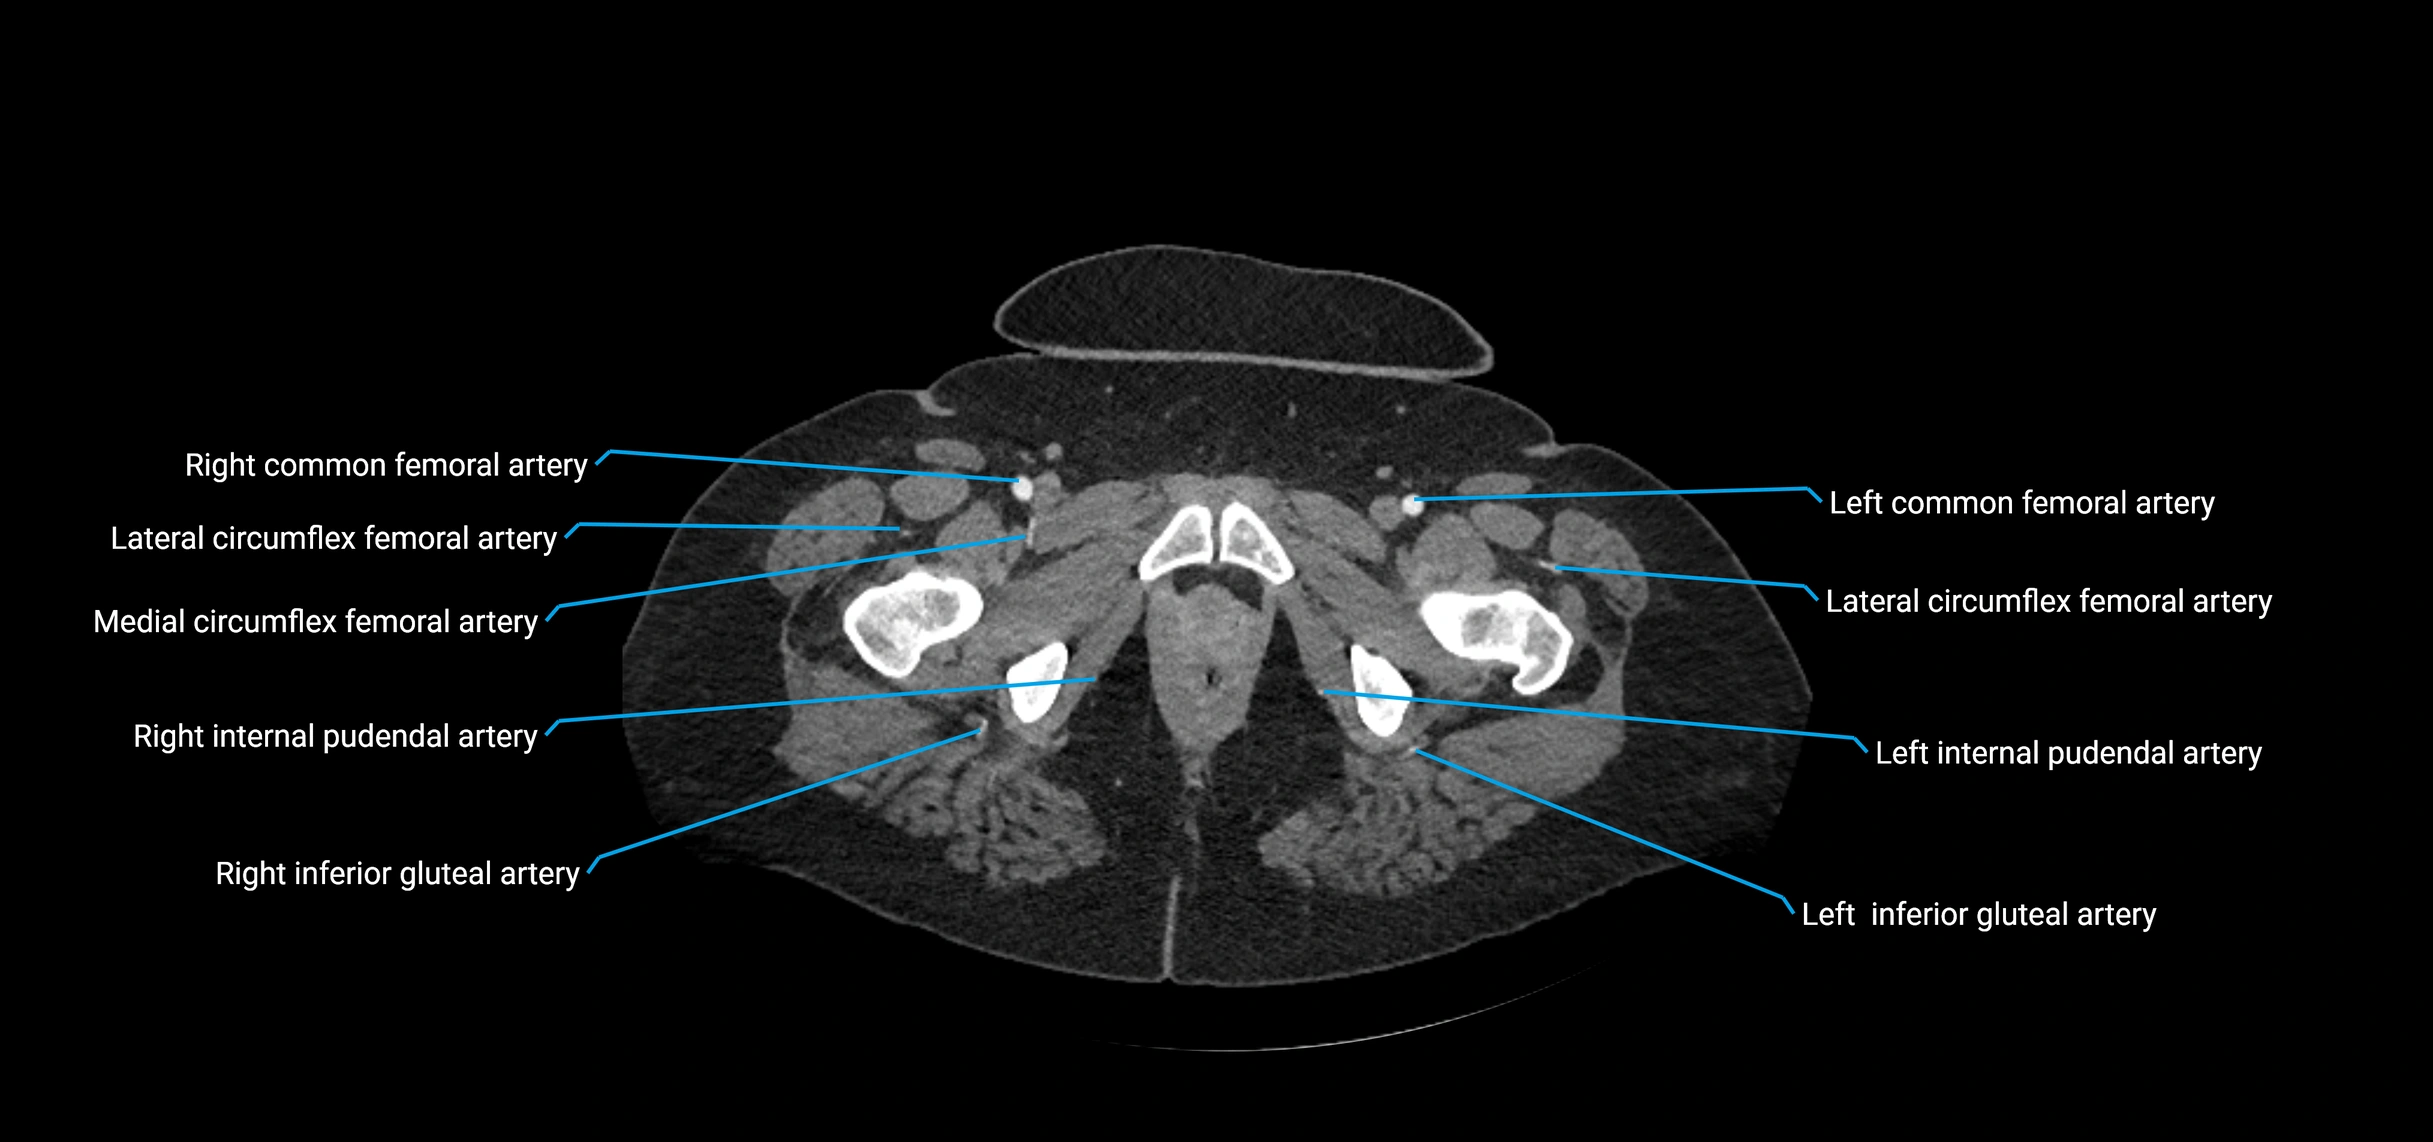

CT images

image

Contrast-enhanced CT (CTA):

• Gold standard for abdominal aortic imaging

• Provides excellent detail of lumen, wall, aneurysm, thrombus, and branch vessels

• Multiplanar and 3D reconstructions help in aneurysm measurement, stent graft planning, and dissection evaluation